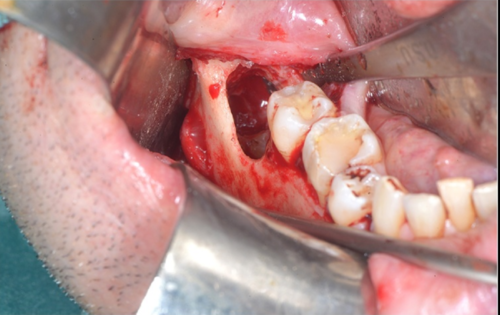

临床分为3期:Ⅰ期有死骨出现但无明显临床症状;Ⅱ期病变局限在牙槽骨内,死骨暴露,并有红肿疼痛等感染症状,伴或不伴口内瘘管;Ⅲ期病变超出牙槽骨范围出现死骨,伴疼痛、感染,并至少伴有病理性骨折、口外瘘管、下颌骨下缘或鼻窦底部骨质溶解破坏3 项之一。

根据此标准,BONJ 的诊断并不困难。目前,BONJ 的发生机制尚不清楚,有人认为可能与BP 药物抑制破骨细胞功能、诱导凋亡、微血管栓塞、创伤和感染等因素有关。结合相关文献,BONJ 静脉和口服药物的发病率分别约为1%和0. 002%。目前,BONJ 尚缺乏理想的治疗方法,临床上主要使用刮除死骨、冲洗创面,高压氧等方法治疗。但是疗效并不确切,有相当大比例的患者病情迁延不愈,因此BONJ 重在预防。

双膦酸盐导致的颌骨骨坏死,虽然无药可治,但在很大程度上是可以预防的。如果要进行双膦酸盐类药物的治疗,不管是口服还是静脉用药,在用药前,请到口腔科进行口腔的全面检查,在用药前将不能保留的残根、智齿、松动牙等拔除,对于正在发炎或有潜在发炎的牙齿,如龋齿、牙周炎,需进行相应的治疗,避免其在之后因发炎诱发颌骨骨坏死。而且在进行双膦酸盐药物治疗后,定期口腔检查,及早发现并治疗口腔内病灶,保持良好的口腔卫生。